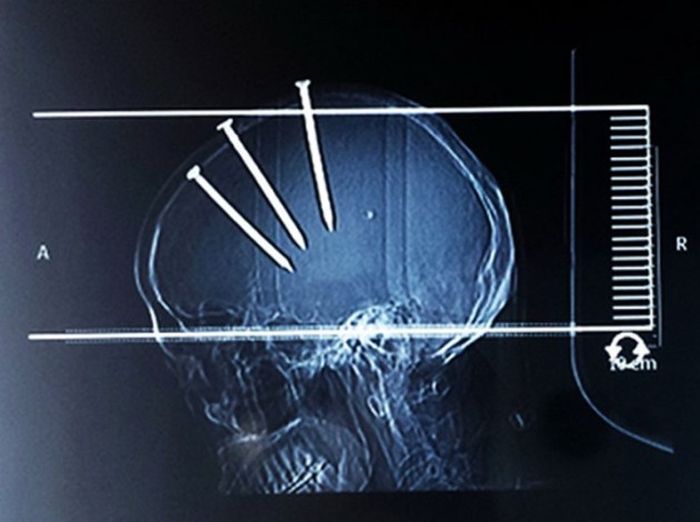

Жуткие рентгеновские снимки

Порой даже не верится, с какими странными и необычными повреждениями в травматологию могут поступить пострадавшие. Всю эпичность профессии врачей травматологии могут с легкостью подтвердить рентгеновские снимки. Просто жесть, да и только..